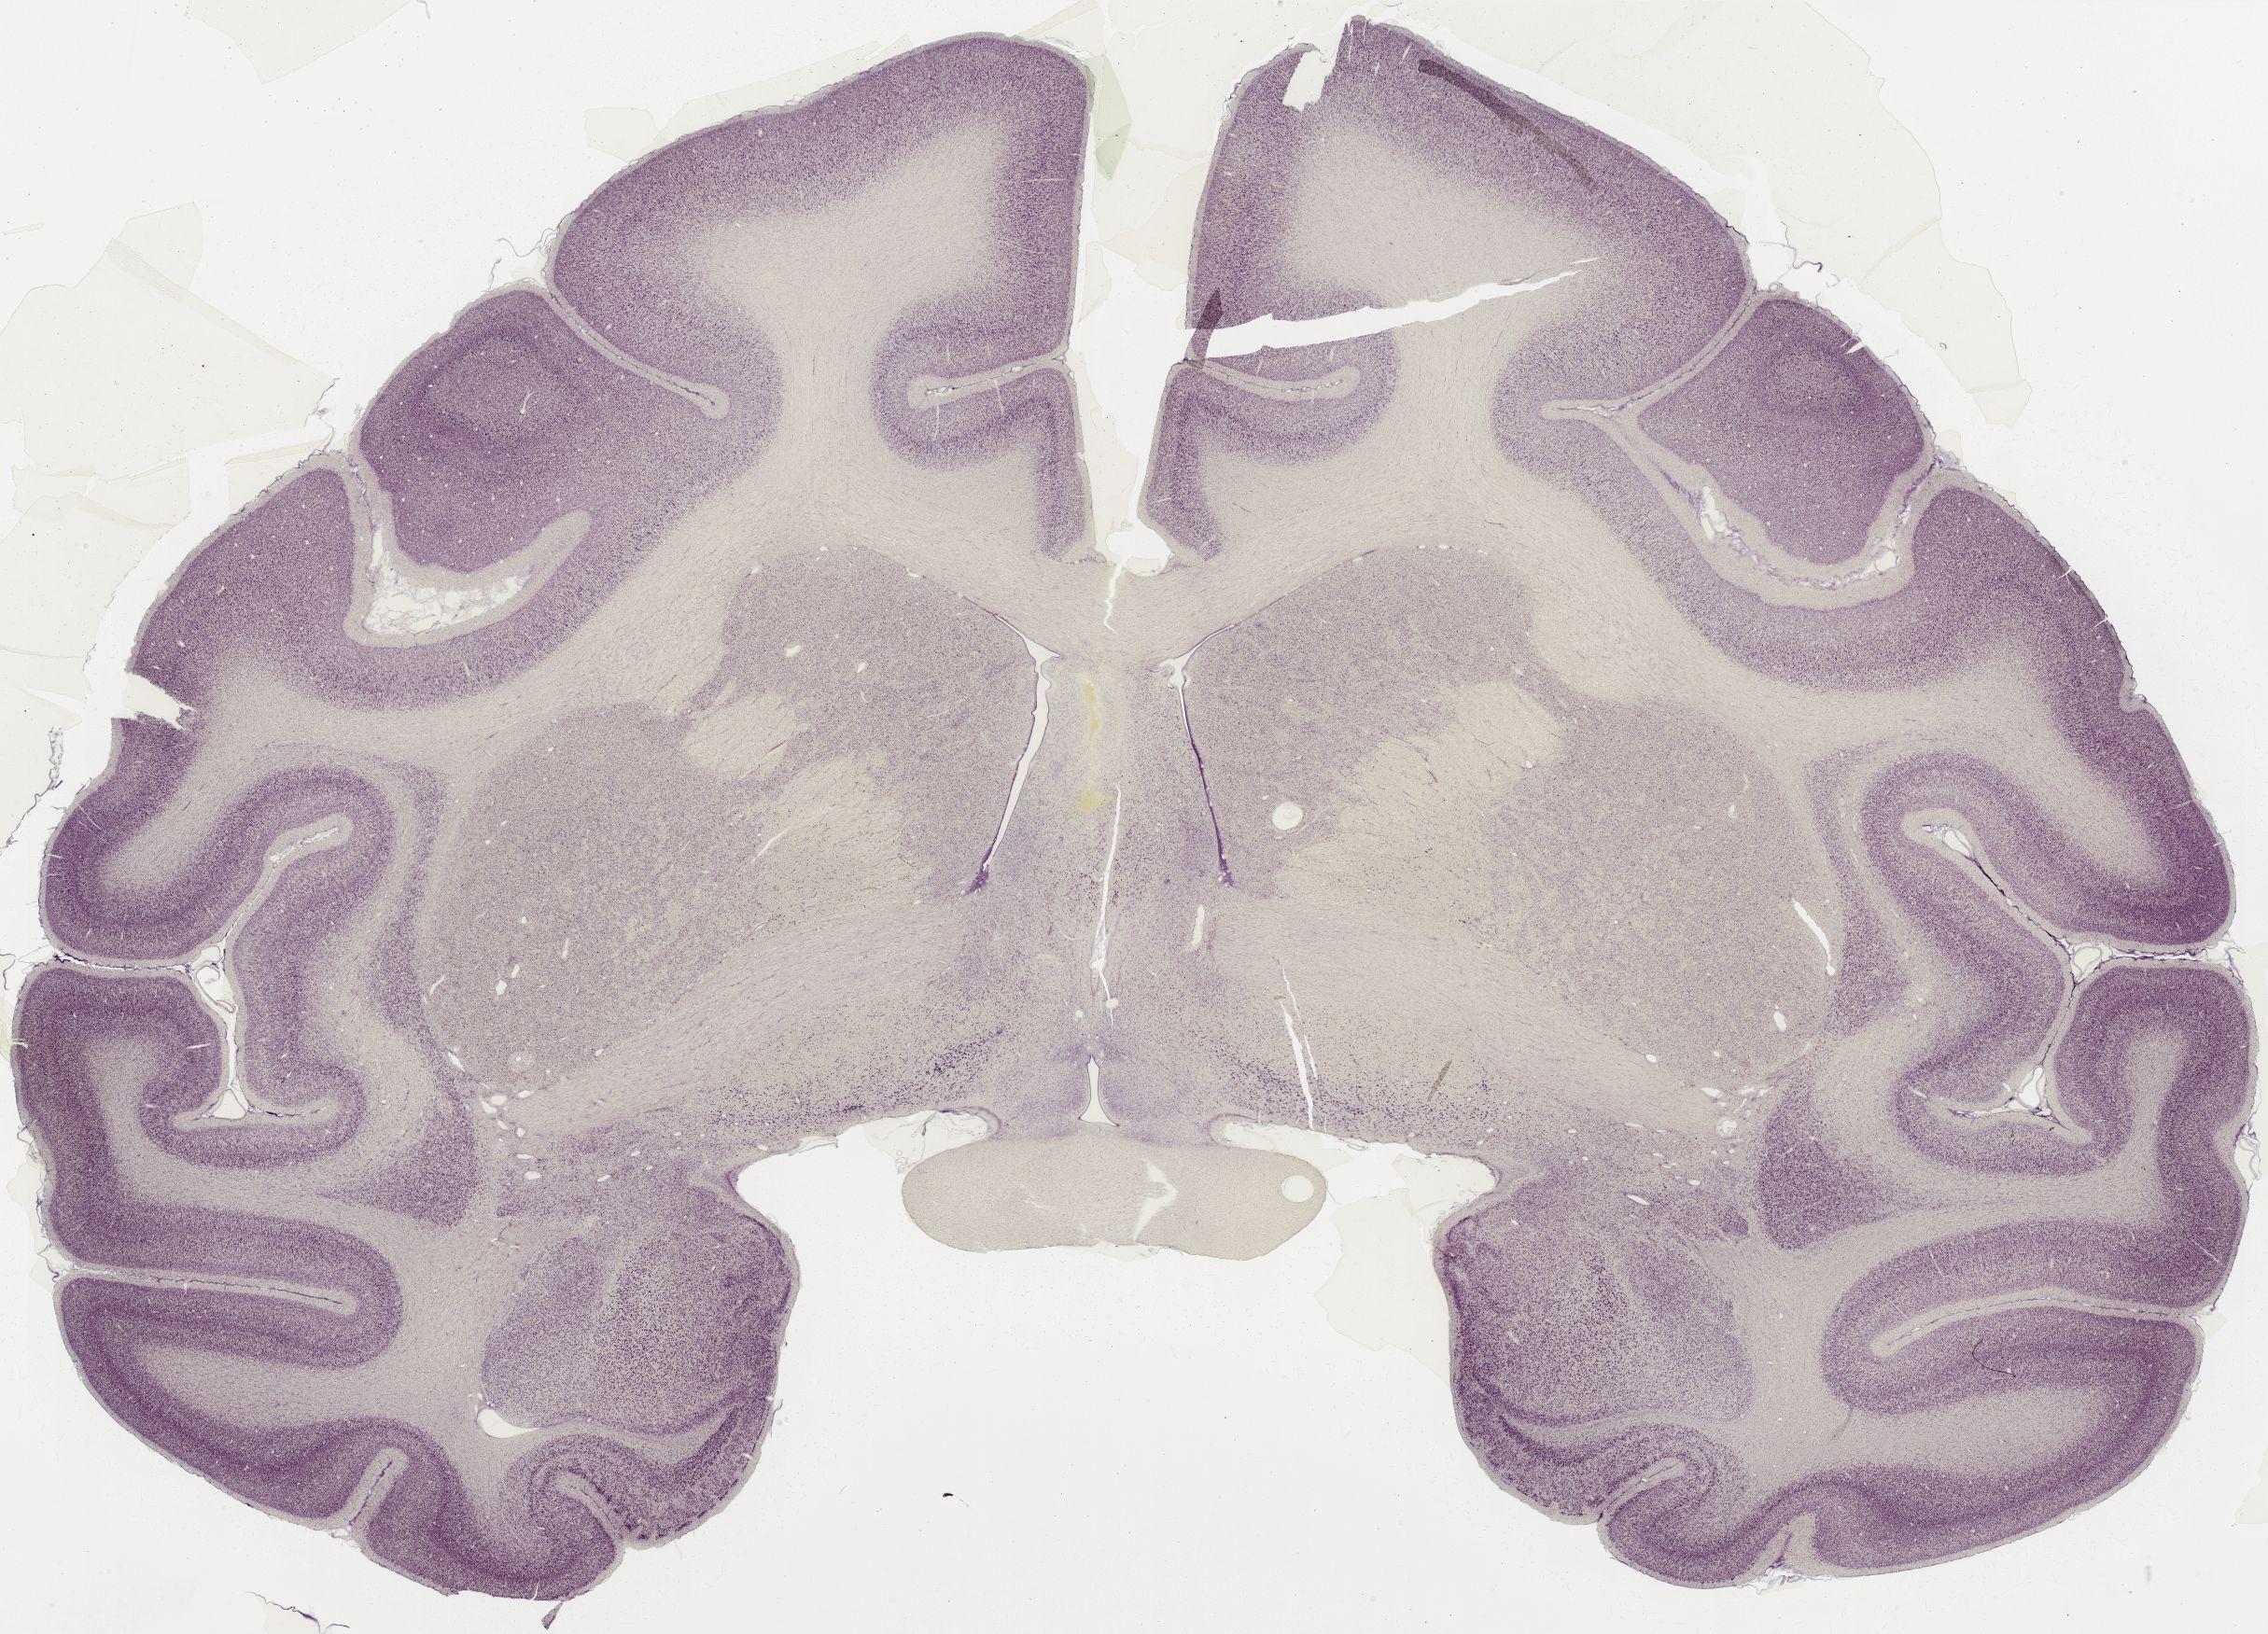

Datasets -> Macaca Mulatta -> Nissl, coronal, histo, Whole-Brain, adult [ Metadata ] · Source: Edward G. JonesDisplaying Sections 1 thru 40 of 56 Sections for this DatasetPages: 1 2 1339 - labeled 1301 - labeled 1251 - labeled 1201 - labeled 1151 - labeled 1102 - labeled 1051 - labeled 1040 - labeled 1020 - labeled 1006 - labeled 1001 - labeled 0982 - labeled 0975 - labeled 0958 - labeled 0951 - labeled 0941 - labeled 0924 - labeled 0920 - labeled 0901 - labeled 0894 - labeled 0878 - labeled 0875 - labeled 0859 - labeled 0851 - labeled 0845 - labeled 0824 - labeled 0823 - labeled 0801 - labeled 0800 - labeled 0785 - labeled 0781 - labeled 0771 - labeled 0770 - labeled 0732 - labeled 0721 - labeled 0720 - labeled 0701 - labeled 0682 - labeled 0680 - labeled 0666 - labeledPages: 1 2